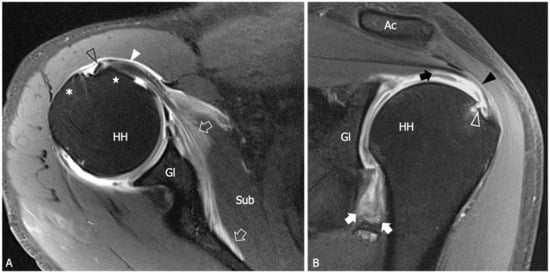

Figure 4.

Adhesive capsulitis in a 45 year old man with severe limitation of the glenohumeral ROM after a trauma, who was submitted for an MRA for a suspected labral tear. (A) Axial and (B) Coronal tSE fat-suppressed T1-weighted MR images obtained after intraarticular injection of gadolinium demonstrate anterior extravasation of the contrast medium (outlined arrows) into and underneath the subscapularis muscle (Sub) as a consequence of capsular stiffness and fissuration. Note the abnormally low distension of the axillary recess (arrows) and its markedly thickened walls. In (B) a partial thickness tear (white outlined arrowhead) of the articular side of the supraspinatus tendon (black arrowhead) is also evident. In effect, the tear involves both the inner fibers of the supraspinatus and the joint capsule, which are merged at this level to form the superior complex. As a consequence, note the superior migration of the contrast outside the joint cavity (black arrow). Black outlined arrowhead, long head of the bicep tendon; white arrowhead, subscapularis tendon; asterisk greater tuberosity; star, lesser tuberosity; HH, humeral head; Gl, glenoid; Ac, acromion.